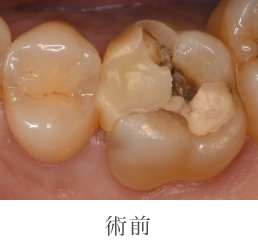

むし歯治療の詳細

- 主訴

- 他院で金属か自費を勧められたが、保険で白い歯にしたい(当院へのセカンドオピニオンで受診)

- 治療期間

- 1週間

- 治療内容

- 虫歯の除去 印象 CAD/CAM Inセット

- 治療のリスク

- 術後しみる可能性があります

- 治療費

- 保険診療に準ずる